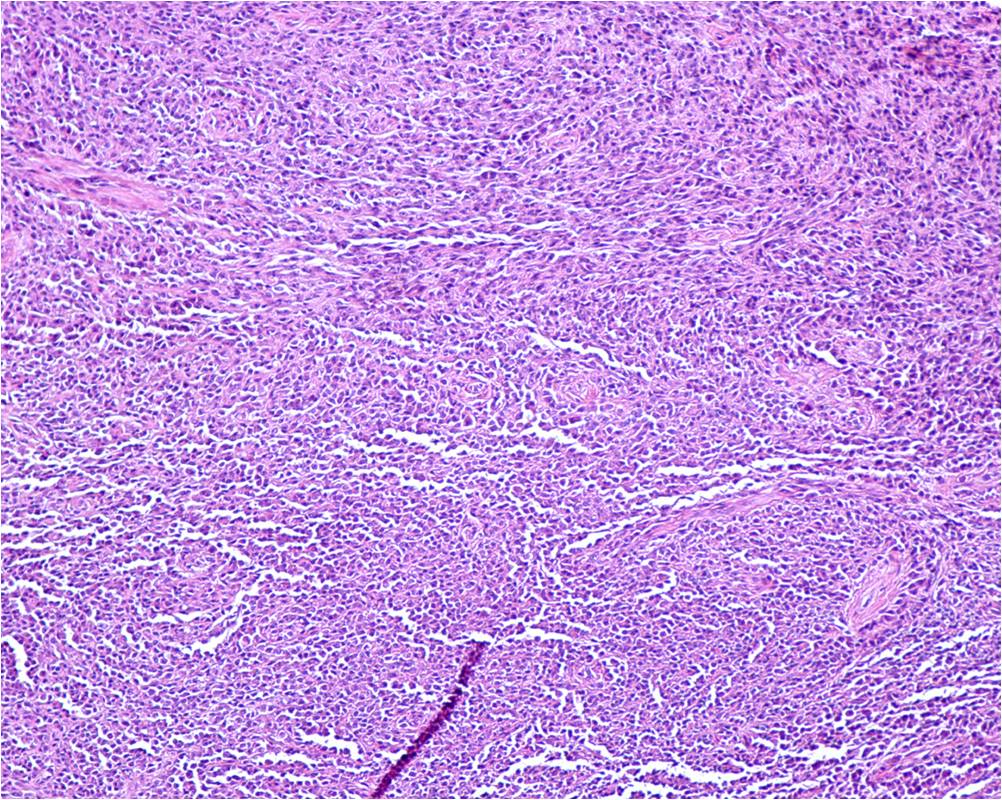

Fig. 6

Fig. 5-7: Microscopic Pathology. Low (Fig. 5), Intermediate (Fig. 6) and High (Fig. 7) power view shows polygonal and elongated shaped cells with acidophilic cytoplasm and prominent nucleoli, with fascicular growth pattern, delineated by fibrous septa. There is a considerable amount of clear cytoplasm around the atypical epithelioid nuclei. There is minimal pleomorphism, low mitotic rate and no evidence of necrosis.